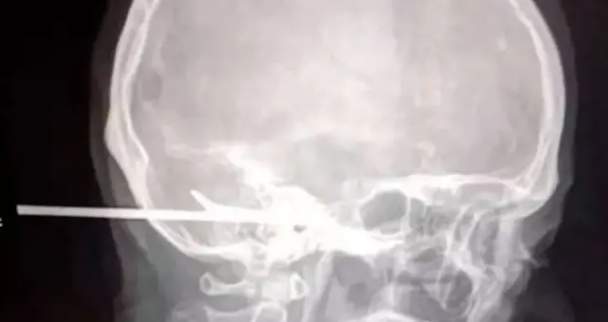

Radiografía del cráneo atravesado con un arpón - 20 minutos

A tan solo unos centímetros de haberle causado daños cerebrales e incluso la muerte se quedó el arpón que le clavaron a un hombre tras una pelea en Tailandia

El pescador Sujit Klingtalay, de 45 años, fue salvado por unos médicos tailandeses que consiguieron quitarle el arpón sin producirle ningún daño como secuela. Sus amigos le llevaron rápidamente al hospital una vez herido a pesar de que la víctima seguía consciente en todo momento.

La cirugía fue delicada y peligrosa, los voluntarios incluso tuvieron que cortar la herramienta antes de realizarle la operación, con mucho cuidado de que a la vez, esta no se desplazase ni se moviese.